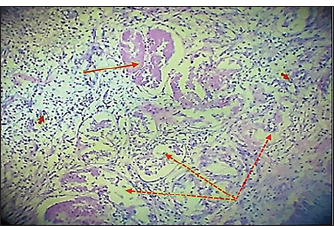

Histopathological evaluationThe zinc gluconate groupIn the GI group, 30 days post-injection, the testes section showed atrophy of the tubuli recti with dilatation of others, desquamation of the tubuli recti epithelium, infiltration of inflammatory cells, and degeneration of seminiferous tubules (Fig. 4). Fibroblast proliferation was observed around the thickened walls of blood vessels (Fig. 5). Other sections showed complete seminiferous tubule stroma necrosis with necrosis in tunica albuginea (Fig. 6). Despite the presence of Leydig cell clusters, some sections displayed germinal cell exfoliation in the lumen of seminiferous tubules accompanied by edematous interstitial tissue and inflammatory cell infiltration (Fig. 7).

Fig. 4. Histopathological section of testes from a dog in the zinc gluconate group at 30 days post-intrasticular injection, showing atrophy of the tubuli recti (black arrow) with dilatation of other (dotted black arrow) , disequilibrium of the tubuli recti epithelium (red head), infiltration of granulation inflammatory cells (red arrow), and degeneration of seminiferous tubules (yellow arrow), (H & E stain 10X).

Fig. 5. Histopathological section of testes from dogs in the zinc gluconate group at 30 days post-intratestinal injactin, showing degeneration of the tubule in the testis recti (black dotted arrow), granuloma (black arrow), congestion (red arrow), thickening wall of blood vessels (red dotted arrow), and proliferation of fibroblasts (yallow arrow),(H & E stain 10X).

Fig. 6. Histopathological section of testes from a dog of the zinc gluconate group at 30 days post-intrasticular injection, showing complete necrosis of seminiferous tubules (red stars) and stroma (black arrow), with necrosis in tunica albuginea(red dotted arrow)(H & E stain 10X).

Fig. 7. Histopathological section of testes from a dog in the zinc gluconate group at 30 days post-intrasticular injection, showing exfoliation of germ cells (red arrows), infiltration of inflammatory cells (white arrows), Leydig cell clusters (yellow arrow), edema (star), and congestion (yellow head arrow) (H & E stain 10X). Surgical groupIn the surgical group (GII), the main characteristic findings at 30 days post-surgery were degeneration of seminiferous tubules, multinucleated spermatid, infiltration of inflammatory cells, atrophy of Leydig cells, and vacuole degeneration of basal and Sertoli epithelium (Fig. 8). Furthermore, there was loss of the straight shape of the tubuli recti, disequimentaion of the tubuli recti epithelium, and proliferation of myoid cells (Fig. 9). Other sections showed coagulative necrosis and ghost tubules in the rete testis (Figs. 10 and 11).